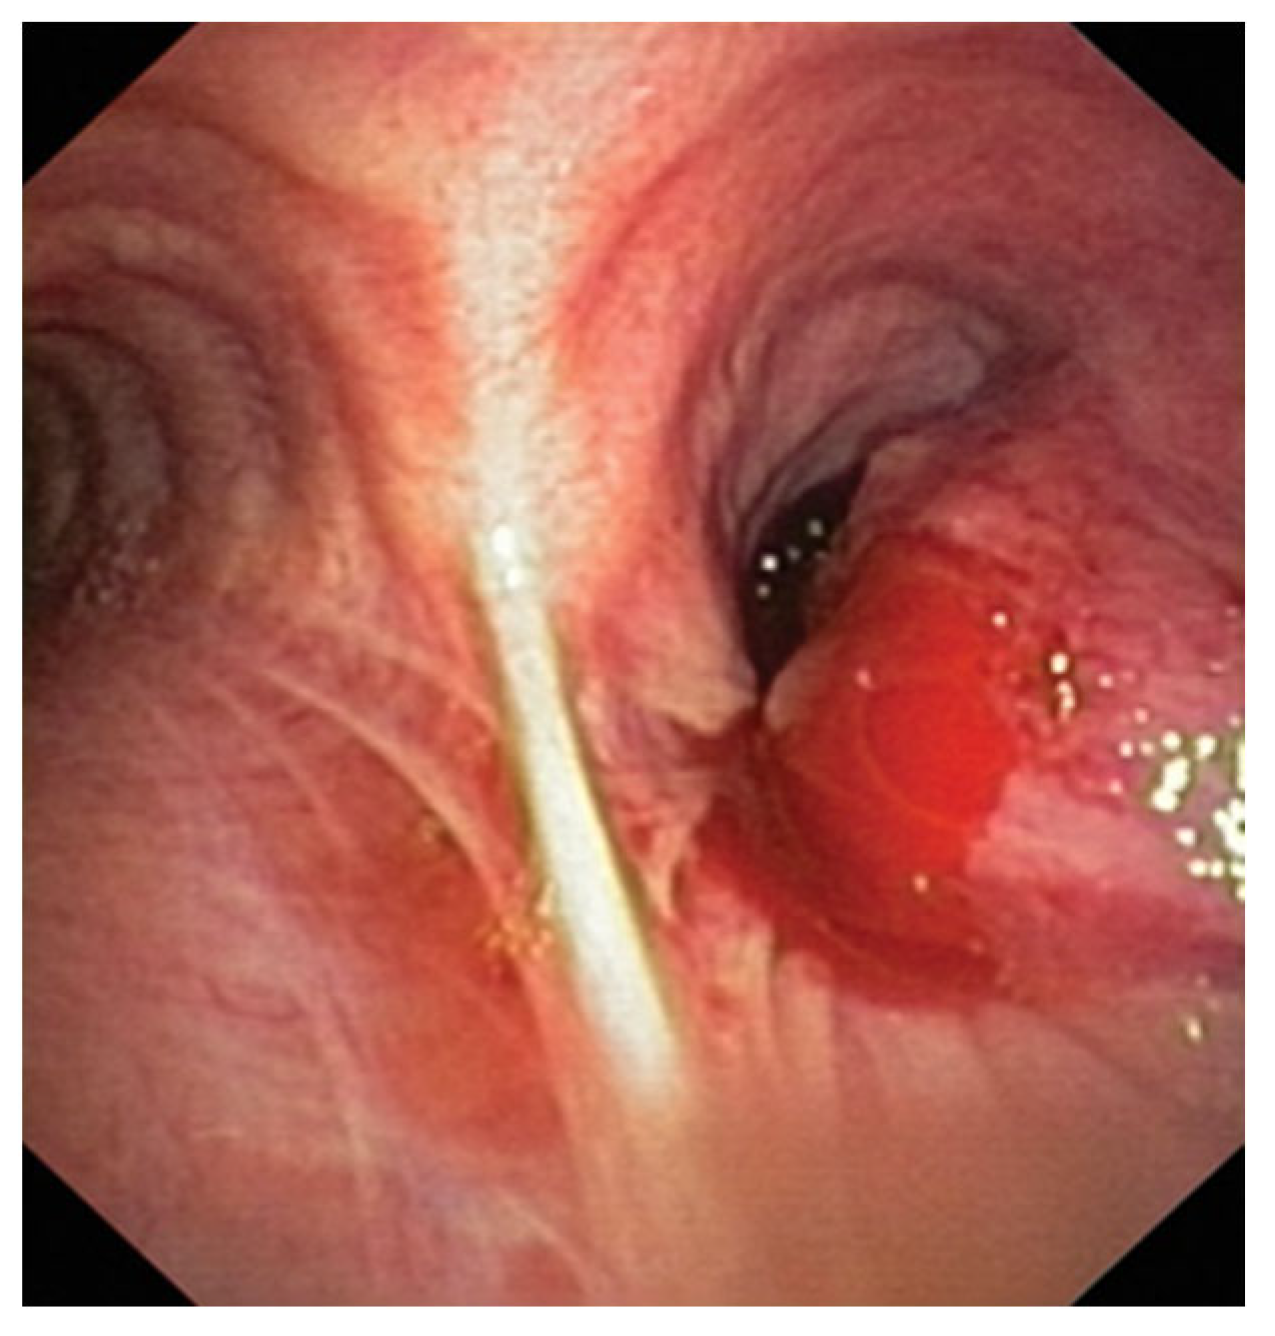

2.1. Cryobiopsy for Endoscopy Visible Tumor Lesions and Transbronchial Cryobiopsy for Peripheral Tumor Lesions—Application of Molecular Tests

- Hetzel, J.; Eberhardt, R.; Herth, F.J.; Petermann, C.; Reichle, G.; Freitag, L.; Dobbertin, I.; Franke, K.J.; Stanzel, F.; Beyer, T.; et al. Cryobiopsy increases the diagnostic yield of endobronchial biopsy: A multicentre trial. Eur. Respir. J. 2012, 39, 685–690. [Google Scholar] [CrossRef]

- Rubio, E.R.; le, S.R.; Whatley, R.E.; Boyd, M.B. Cryobiopsy: Should this be used in place of endobronchial forceps biopsies? Biomed. Res. Int. 2013, 2013, 730574. [Google Scholar] [CrossRef]

- Simon, M.; Simon, I.; Tent, P.A.; Todea, D.A.; Haranguș, A. Cryobiopsy in lung cancer diagnosis—A literature review. Medicina 2021, 57, 393. [Google Scholar] [CrossRef] [PubMed]